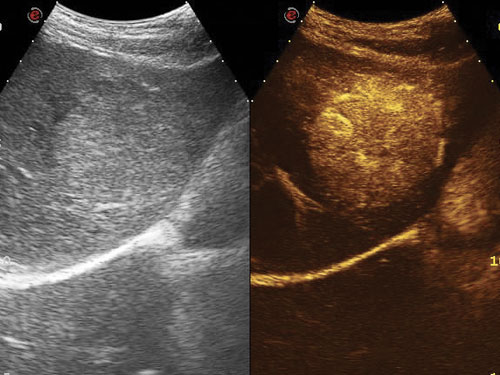

CnTI ™ Contrast Tuned Imaging: Vysoká citlivost, hluboká penetrace a vysoké rozlišení jsou běžné vlastnosti technologie CnTI ™ Contrast Enhanced Imaging pro lepší diagnostický výkon.